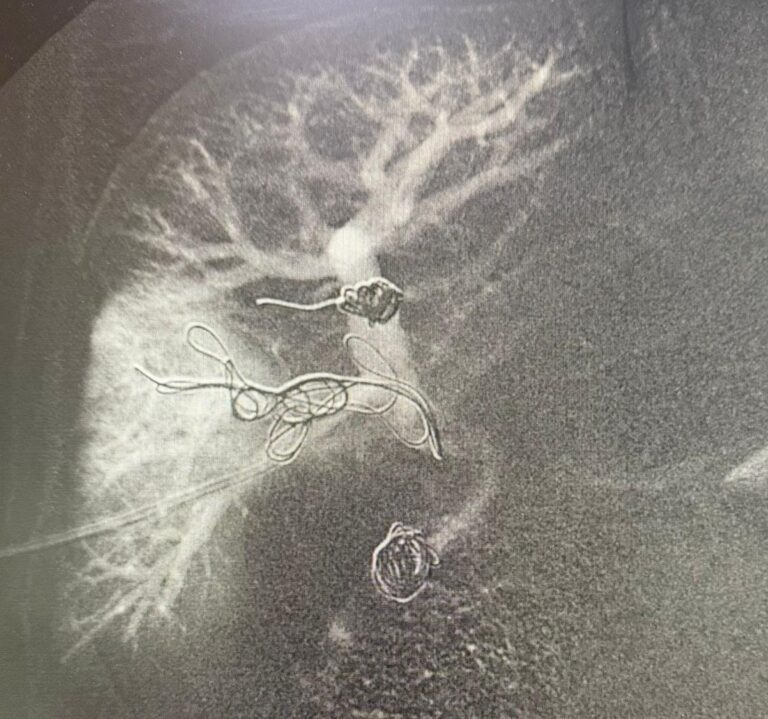

A intervenção foi conduzida pelos cirurgiões vasculares e endovasculares Romulo Bizare e Silfayner Dias e consistiu na embolização da veia porta, principal veia do fígado, por meio de punção trans-hepática percutânea guiada por ultrassom, considerada de alta complexidade.

Como parte desse preparo, foi realizada a punção trans-hepática dos ramos portais direitos, seguida da embolização, com a introdução de materiais específicos, como molas e partículas, nas veias hepáticas para interromper o fluxo sanguíneo na área afetada.

O procedimento foi executado na sala de hemodinâmica, por meio de punção na região do abdômen guiada por ultrassom e com uso de instrumentos de alta precisão.